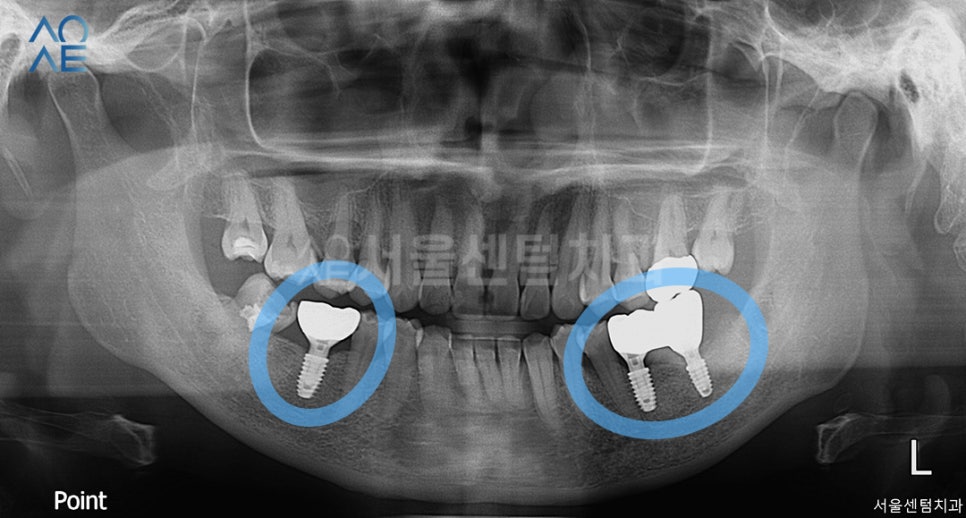

저번과 마찬가지로 골유착을 하면서

튼튼하게 고정되기를 기다리며

정기체크를 진행했습니다.

다행히 환자분께서는 자주 내원하시면서

계속 체크 받으시고 소통해주셔서

치료에 불편함 없이 진행되었습니다.

이렇게 치아상실 공간에

총 3개의 임플란트를 식립하였습니다.

픽스쳐가 골유착을 하면서 튼튼하게 고정되고

잠시 임시보철을 올려드려서

일상생활에 불편함 없이 지내도록 도와드립니다.